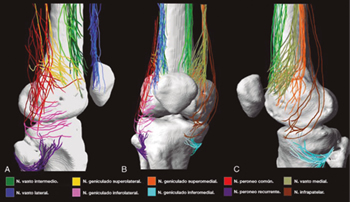

Although there is general agreement that the branches that innervate the knee joint capsule come from the femoral, sciatic, and obturator nerves, there is no consensus on the origin and number of branches innervating this area (Table I). To understand the innervation of the knee joint capsule, we divide it into two compartments: An anterior and a posterior (10). The innervation of the posterior articular capsule originates from the tibial nerve and the posterior division of the obturator nerve (11,12). The innervation of the anterior articular capsule (Figure 1) is divided into 4 quadrants (13,14): The lateral superior quadrant is innervated by the vastus lateralis nerves (VLN), vastus intermedius nerve (VIN, superior lateral genicular nerve (SLGN), and common peroneal nerve (CPN). The inferolateral quadrant receives innervation of the inferior lateral genicular (ILGN) and recurrent peroneal (RPN) nerves. The medial superior quadrant is innerved by the nerves of the vastus medialis (VMN), VIN, and superior medial genicular nerve (SMGN). The medial inferior quadrant receives innervation of the inferior medial genicular nerve (IMGN) and in some cases of the infrapatellar branch of the saphenous nerve (IPBSN).

Fig. 1. Innervation of the anterior knee joint capsule. A. Lateral view. B. Anterior view. C. Medial view. Image taken from Tran et al. (13). Reproduced with the permission of Philip Peng Educational Series.